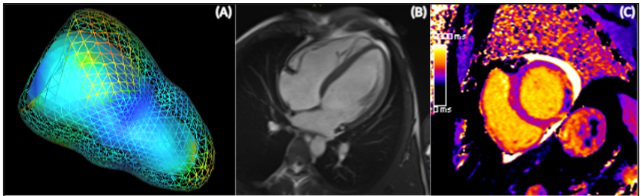

Cardiac Magnetic Resonance Tomography and Myocardial Infarction

Leader: Univ.-Prof. Dr. Bernhard Metzler

Members: Priv.-Doz. Dr. Sebastian Reinstadler, PhD; Assoz.-Prof. Dr. Gert Klug; Assoz.-Prof.in Dr.in Agnes Mayr, Dr. Martin Reindl, PhD; Dr.in Christina Tiller; Dr.in Magdalena Holzknecht; Dr. Ivan Lechner, PhD Student; Dr. Felix Troger, PhD Student

The working group on “Cardiac Magnetic Resonance Tomography (CMR)”, led by Univ.-Prof. Dr. B. Metzler, MSc was founded in 2002 and has published over 133 original research papers in peer-reviewed journals since that time. One of its main focuses is on CMR imaging in patients with ST segment elevation myocardial infarction (STEMI), to obtain deeper insights into the pathophysiology of myocardial tissue injury, infarct healing and myocardial remodelling. The assessment of degenerative aortic valve stenosis and CMR-guided transcatheter aortic valve implantation (TAVI) planning is another important focus of the research group. The working group is also involved in randomised, multicentre, multinational clinical trials. The study group is based on close cooperation between the University Clinic for Internal Medicine III, Cardiology and Angiology (Head: Univ.-Prof. Dr. A. Bauer) and the Department of Radiology (Head: Univ.-Prof.in Dr.in E. Gizewski) at the Medical University of Innsbruck. Univ.-Prof. Metzler’s team consists of two associate professors, one senior physician, three fellows and two PhD students as well as a current total of 7 diploma students. Between 2018 and 2020, the working group published 24 peer-reviewed original research articles and obtained nine research grants, including the renowned “Hans-Blömer-Young Investigator Award”, the “Paracelsus prize” and the “Werner-Klein Research Prize”. International cooperation was initiated with the CMR working groups of Prof. Dr. H. Thiele at the University of Leipzig in Germany and Prof. Dr. I. Eitel at the University of Lübeck in Germany, with another seven publications. Future aims include the establishment of extended cooperation with centres in Austria, in order to perform randomised multicentre CMR studies.